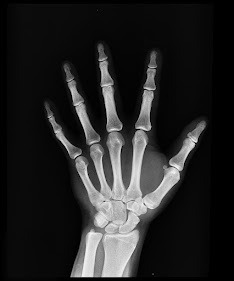

Una fractura es la rotura total o parcial de un hueso. O dicho de otra manera, es la pérdida de continuidad normal de la sustancia ósea o cartilaginosa a consecuencia de golpes, fuerzas o tracciones cuyas intensidades superan la elasticidad del hueso. Las fracturas se pueden clasifican:

Corriendo habrá que tener cuidado con las fracturas que se pueden producir como resultado de un mal apoyo y las fracturas que se produzcan por estrés. Este tipo de lesiones probablemente nos mantendrán apartados de correr durante unos meses.

Fractura por estrés

Los corredores que realizan la carrera a pie con cierta frecuencia y sobre todo los ultra fondistas pueden sufrir este tipo de fracturas, que se suelen producir principalmente por dos motivos:

Por una mala técnica.

Por sobre entrenamiento.

Ocurren como consecuencia de una reiteración prolongada en el tiempo y repetitiva de fuerzas o micro traumatismos de bajo impacto, que se producen en las zonas de presión o de excesivo roce. Lo que se traduce en una sobrecarga mecánica continuada.

Los huesos están formados por colágeno. Este material se encarga de reponer los desperfectos que pueden sufrir los huesos y de reparar los daños producidos. Si los daños superan la capacidad regenerativa de este material es cuando se crea la temida fractura. Debido al impacto, los huesos más frecuentes de sufrir este tipo de fractura en corredores de fondo son:

El maléolo interno del tobillo.

Los metatarsos del pie.

Inicialmente se siente un dolor moderado, debido a la continua actividad de correr que se acentúa con el tiempo. Llegados a este punto si se guarda reposo es suficiente para evitarla. Durante un tiempo podemos realizar otros deportes que no tengan un elevado impacto para nuestras articulaciones como por ejemplo nadar, para no perder la forma física. Pasado un tiempo y si las molestias desaparecen podemos volver a entrenar la carrera a pie.

Pero si no guardamos el debido reposo y seguimos corriendo sin hacer caso a las señales de nuestro cuerpo, el hueso poco a poco se va fisurando, hasta que finalmente se fractura. Los síntomas pueden durar semanas y suelen ser dolor localizado, enrojecimiento, edema y aumento de la temperatura.

En ocasiones no resulta fácil distinguir una fractura por estrés ya que podemos confundirlas con lesiones musculares, por lo que si sufrimos un dolor continuado lo aconsejable será descansar y si los síntomas no desaparecen debemos acudir al médico para que nos realicen alguna prueba para determinar la posible lesión. Las fracturas se pueden dividir atendiendo al origen de su producción en dos tipos:

Fracturas por debilidad . Son el resultado de deficiencias óseas (se suelen dar en ancianos, niños, personas propensas al desarrollo de esta lesión, etc...)

Fracturas por fatiga. Este tipo de fracturas suele dar en deportistas. Se producen como consecuencia de una desmesurada y continua actividad realizada, como por ejemplo correr. Poco a poco se produce el debilitamiento del hueso hasta que no puede aguantar más. Evidentemente esta es la fractura que nos suele afectar como corredores.

Estas fracturas no suelen implicar traumatismos para la estructura ósea dañada, por lo que a la hora de la recuperación esto les favorece y facilita la rehabilitación. El tiempo de recuperación tras una fractura por estrés oscila entre seis y ocho semanas, en las que tendremos que guardar reposo. Para evitar a la larga estas fracturas, podemos realizar varias cosas para prevenir su patología: